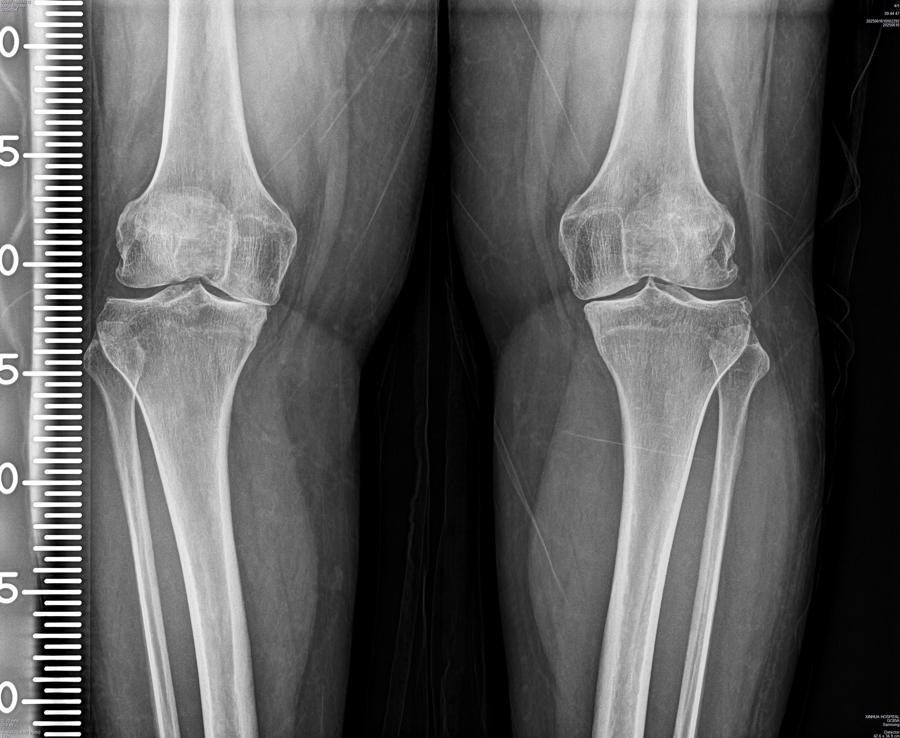

骨关节炎影响着全球约5亿人,相当于每14个人中就有1人深受其害。这种疾病会导致关节软骨逐渐磨损,引发疼痛、肿胀和活动受限。目前的药物治疗只能暂时缓解疼痛,无法阻止疾病进展。

为什么治疗如此困难?原来,软骨组织就像一个致密的网状迷宫,网眼直径只有60纳米,相当于头发丝的千分之一,大于这个尺寸的药物颗粒根本进不去。即使是小分子药物进入关节腔,也会在几小时内被滑液冲走。更棘手的是,病变的软骨细胞在关节中分布不均,现有技术无法区分哪些是正常细胞,哪些是病变细胞。